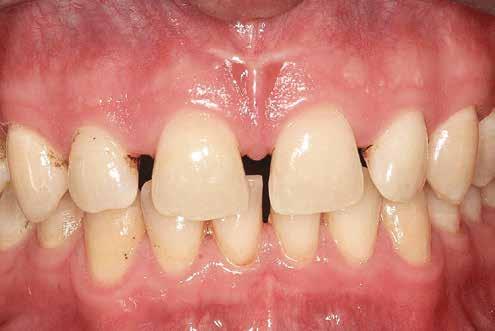

Lány páciensem I. fázisú kezelését 10 évesen kezdtük el bimaxilláris funkciós, kivehető készülékkel. Megfigyelhetőek a class 2-es eltérésnél tipikusan jellemző szűk felső és alsó fo-

gívek, valamint a nagy overjet, a mandibula disztál helyzete, továbbá a felső metszőfogak protrúziója, amelynek kialakulásához sokszor hozzájárul az ujjszopás is (1-3. képek)

A vegyes fogazati kezelési célok a fogívek tágítása és a mandibula meziális irányú növekedésének a biztosítása volt. Fontos, hogy az ilyen típusú készülékeket nem csak éjszaka, hanem napközben is – amennyit csak lehet – hordani kell a minél hatékonyabb működés érdekében. A 18 hónapos első fázisú kezelésnek köszönhetően az alap kezelési célok megvalósultak, sikerült a class 1-es okklúziót beállítani (4-7. képek).